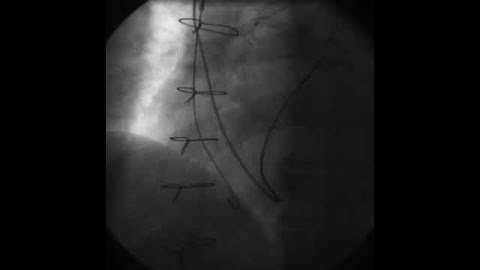

Rotating Pacemaker Fluoroscopic Video